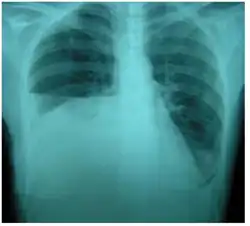

| Right sided pleural effusion caused by urinothorax | |

Abdominal ultrasonography and CT scan can help diagnose the underlying condition of the genitourinary tract. If other methods prove inconclusive, an accurate diagnosis can be made by a technetium-99m kidney scan, which shows albumin labeled with 99Tc that translocates into the pleural space from the genitourinary tract.[4]